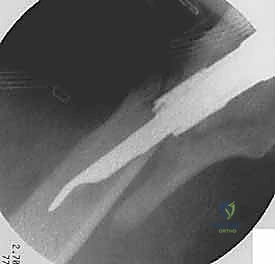

4. توسيع القناة وإدخال المسمار

يتم استخدام أدوات حفر خاصة (Reamers) لتوسيع القناة النخاعية بلطف لتستوعب المسمار المصنوع من التيتانيوم. بعد ذلك، يتم انزلاق المسمار النخاعي الرئيسي داخل العظم حتى يصل إلى العمق المطلوب.

5. تثبيت عنق ورأس الفخذ (المسمار الرأسي)

من خلال ذراع توجيه متصلة بالمسمار الرئيسي، يتم إحداث ثقب في عنق ورأس عظمة الفخذ. يتم إدخال المسمار الرأسي (Cephalic Screw) السميك ليمسك برأس الفخذ بقوة ويسحبه نحو المسمار الرئيسي، مما يضغط الكسر (Compression) ويحفز التئام العظام بسرعة.